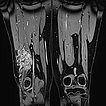

Coronal fat-suppressed T2-weighted MRI of the thighs shows an intramuscular venous malformation on the right thigh (hyperintense).

Axial T2-weighted MRI, fat-suppressed, shows the close relationship to the periosteum of the femur. This location is particularly painful due to inflammatory irritation of the periosteum.

T2-weighted MRI without fat suppression in the axial plane reveals inflammatory, fibrotic remodeling of the lesion due to multiple inflammations. The right vastus lateralis of the quadriceps femoris muscle is completely penetrated by the lesion.